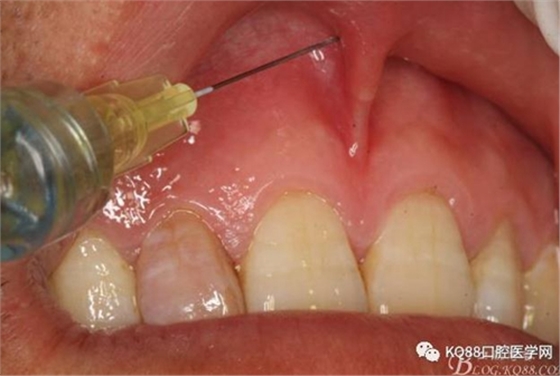

圖4. 唇腭側(cè)局部浸潤(rùn)麻醉行根尖囊腫摘除術(shù)+根管倒充填。唇側(cè)浸潤(rùn)要求進(jìn)針深度比正常麻醉深度要深點(diǎn),因?yàn)檫€有囊腫的摘除。